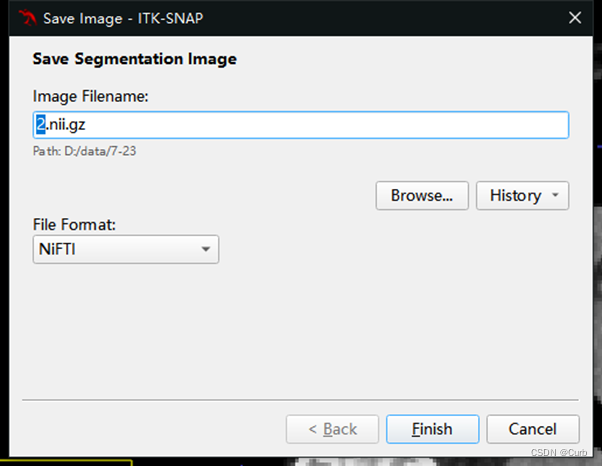

5 分割结果保存

在工具栏的Segmentation中选择 Save Segmentation Image,确定好路径(Browse选择保存路径)和名称(不能包含中文),点击Finish即可。也可以保存为其他格式供选择。